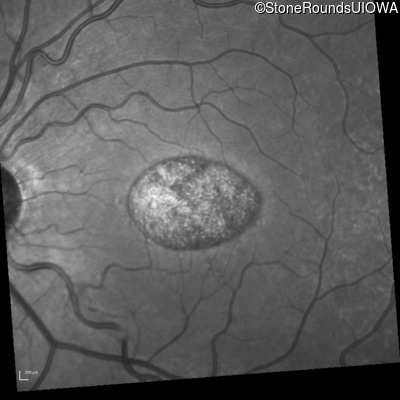

Infrared Fundus Photograph - Right - 20/100 sc

Exemplar